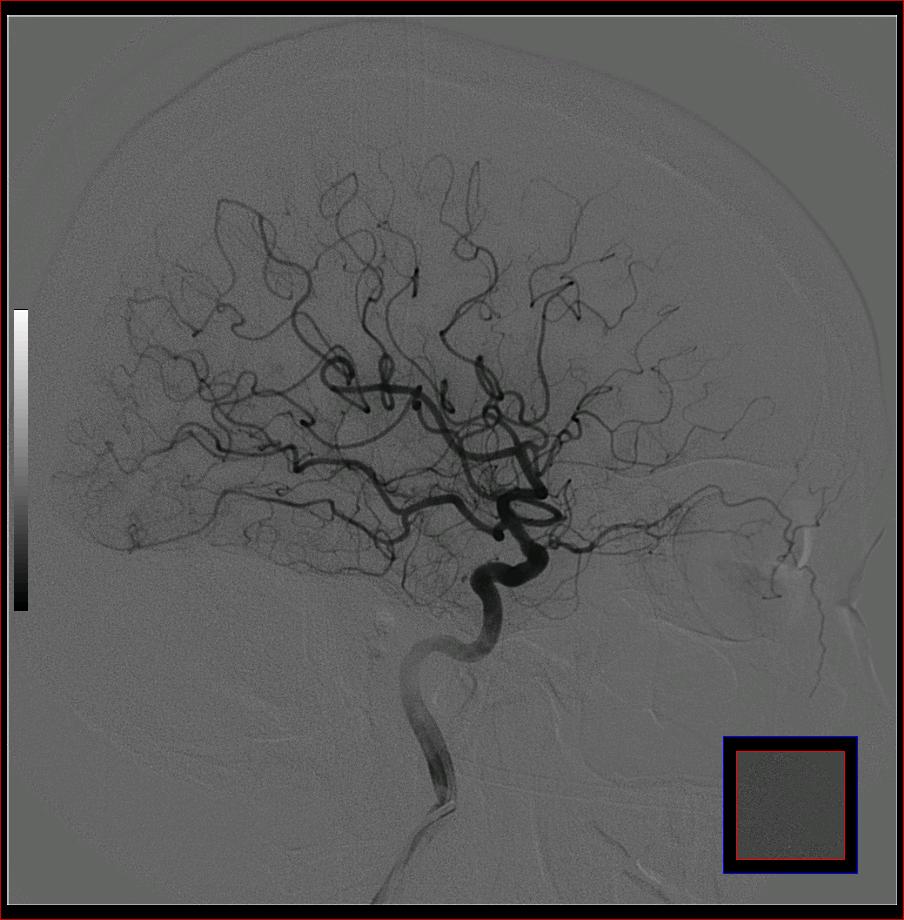

标题: DSA0121:脑血管造影

男,65岁,肢体无力。

左侧大脑中动脉水平段狭窄.

右侧大脑前a缺如.左侧大脑中动脉m1段狭窄,远端分支分布稀疏.

右侧大脑前a缺如.左侧大脑中动脉m1段狭窄

前交通或稍远端动脉瘤要仔细查,左大脑中动脉狭窄要鉴别,有可能是痉挛,因为造影导管插得稍深啦。其它就是供血动脉变异较大

烟雾病